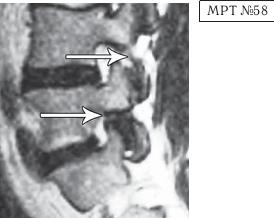

На МРТ № 54 наблюдается изменение физиологического лордоза, стеноз спинномозгового канала, грыжа межпозвонкового диска и спондилёз в сегменте LIII-LIV, ретроспондилолистез — LIV и LV. Как правило, причина вышеупомянутых болей при таких патологиях скрывается в дугоотростчатых суставах. Дело в том, что при изменении физиологического лордоза извращается «работа» и дугоотростчатых суставов. В состоянии нормы дугоотростчатые суставы имеют дугообразную форму и расположены во фронтальной, горизонтальной и сагиттальной плоскостях в среднем под углом 45о. При развитии дегенеративнодистрофического процесса в межпозвонковом диске (снижении высоты диска, возникновении сегментарной нестабильности) происходит смещение суставных поверхностей дугоотростчатых суставов по отношению друг к другу, что в свою очередь приводит к уплощению физиологического лордоза и его кифозированию (МРТ № 55) или же формированию гиперлордоза (МРТ № 56). И в том, и в другом случае данные процессы, как правило, сопровождаются сдавлением спинномозговых корешков (что вызывает соответствующие боли). Кроме того, сами дугоотростчатые суставы хорошо иннервированы, поэтому протекание патологических процессов, с участием этих суставов, сопровождается соответствующими болевыми ощущениями. ![]() На МРТ № 55 наблюдается уплощение физиологического лордоза в поясничном отделе позвоночника. На МРТ № 56 наблюдается гиперлордоз в поясничном отделе позвоночника. На МРТ № 57 наблюдаются нарушения конгруэнтности в дугоотростчатых суставах в сегменте LV—SI (указано стрелкой) вследствие гиперлордоза. ![]() |